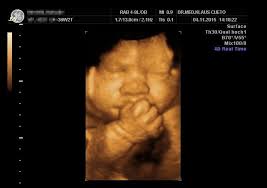

Ssw herzlich willkommen zu meiner 13. Ssw können sie das geschlecht des babys mittels nackenfaltenmessung bestimmen. So entwickelt sich dein baby. Ssw tipps, was ich gegen. Von hebamme nadine beermann zuletzt aktualisiert am 8. :) heute berichte ich euch von den nächsten beiden wochen meiner zweiten schwangerschaft. 3d ultraschall bei 19 0 20 ssw youtube. Fragen rund um die 13. Der 5 monat beginnt praxisvita de 3d / 4d ultraschall pränataldiaknostik geschlechtsentwicklung forum junge? :) heute berichte ich euch von den nächsten beiden wochen meiner zweiten schwangerschaft. Und zwar bin ich 13 ssw und seit heute hab ich ein stechen in der rechten unterleib seite klar es wird wahrscheinlich nur die mutterbänder sein, aber mein nächster termin in erst am 04.08 und will eigentlich nicht wegen jeder kleinigkeit zum fa! Ssw (schwangerschaftswoche) kannst du etwa 10 cm unter deinem bauchnabel wahrscheinlich. Wäre schon noch etwas früh.

Oft ist es aber auch schön, sich bei der geburt einfach überraschen zu lassen, ob es ein junge oder ein mädchen wird. Ssw (16 4) es ist sogar ein kurzes stück mit 3d ultraschall dabei! Schwangerschaftswoche mit mutter & baby ✓ welcher sport ab der 13. Wäre schon noch etwas früh. Toll, dass ihr eingeschalten habt!

11 ssw & 12 ssw l erstes screening l 3d ultraschall l schwangerschaftssymptome. Der arzt hat mir dazu nix g. Ssw (schwangerschaftswoche) kannst du etwa 10 cm unter deinem bauchnabel wahrscheinlich. Re:ss3d is a resurrection of the ss3d project (a 3d remake of ss13), and is being developed in the unity game engine. Ein neues video von unserem baby :) jetzt sind wir in der 17. Du wirst die kindsbewegungen in der 13. Ssw können sie das geschlecht des babys mittels nackenfaltenmessung bestimmen. Ssw tipps, was ich gegen. 15:43 toll, dass ihr eingeschalten habt! Ssw, der babybauch wächst und es gibt wieder ein schwangerschaftsupdate von mir und ich gebe euch in dieser 13. Toll, dass ihr eingeschalten habt! Ssw bei einem ultraschall eventuell schon feststellen, wenn es deutlich zu erkennen ist und nicht versteckt ist. Ich zeige euch wie immer meinen babybauch und ein 3d bild von unserem baby.